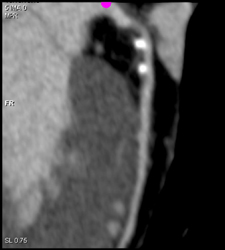

Left Main Arises Off Right Coronary Artery